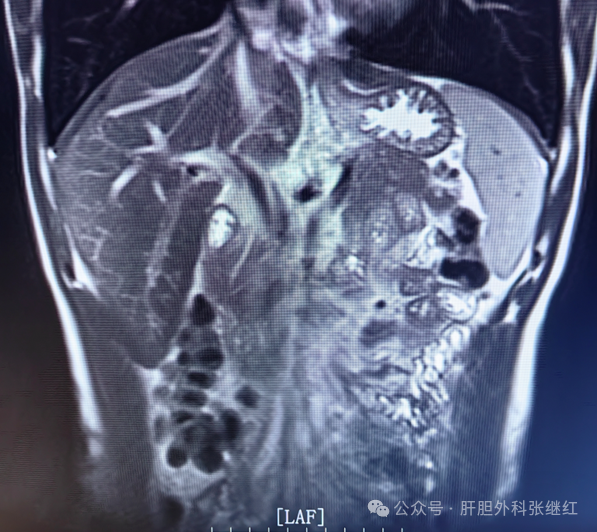

一、精准肝胆胰脾外科手术(开腹手术、腹腔镜手术)

(一)精准肝脏外科手术

1、精准肝切除术

(三)精准胰腺外科手术

1、胰十二指肠切除术

三、复杂肝胆胰脾外科疾病的诊治

(一)中晚期肝癌的综合治疗